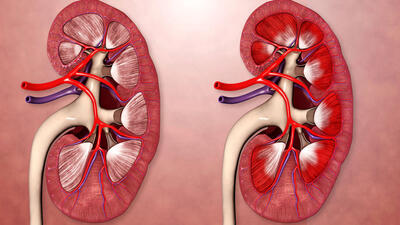

نارسایی کلیه

عدم کنترل قند خون موجب نارسایی کلیه

فوق تخصص کلیه دانشگاه علوم پزشکی بابل عدم کنترل قند خون را موجب نارسایی کلیه دانست.

نارسایی مزمن کلیه یک بیماری خاموش است که فرد مبتلا ممکن است سالها از آن بیاطلاع باشد؛ علل ایجاد کننده این بیماری، اغلب به بیماریهای دیابت و فشار خون بالا بازمیگردد.